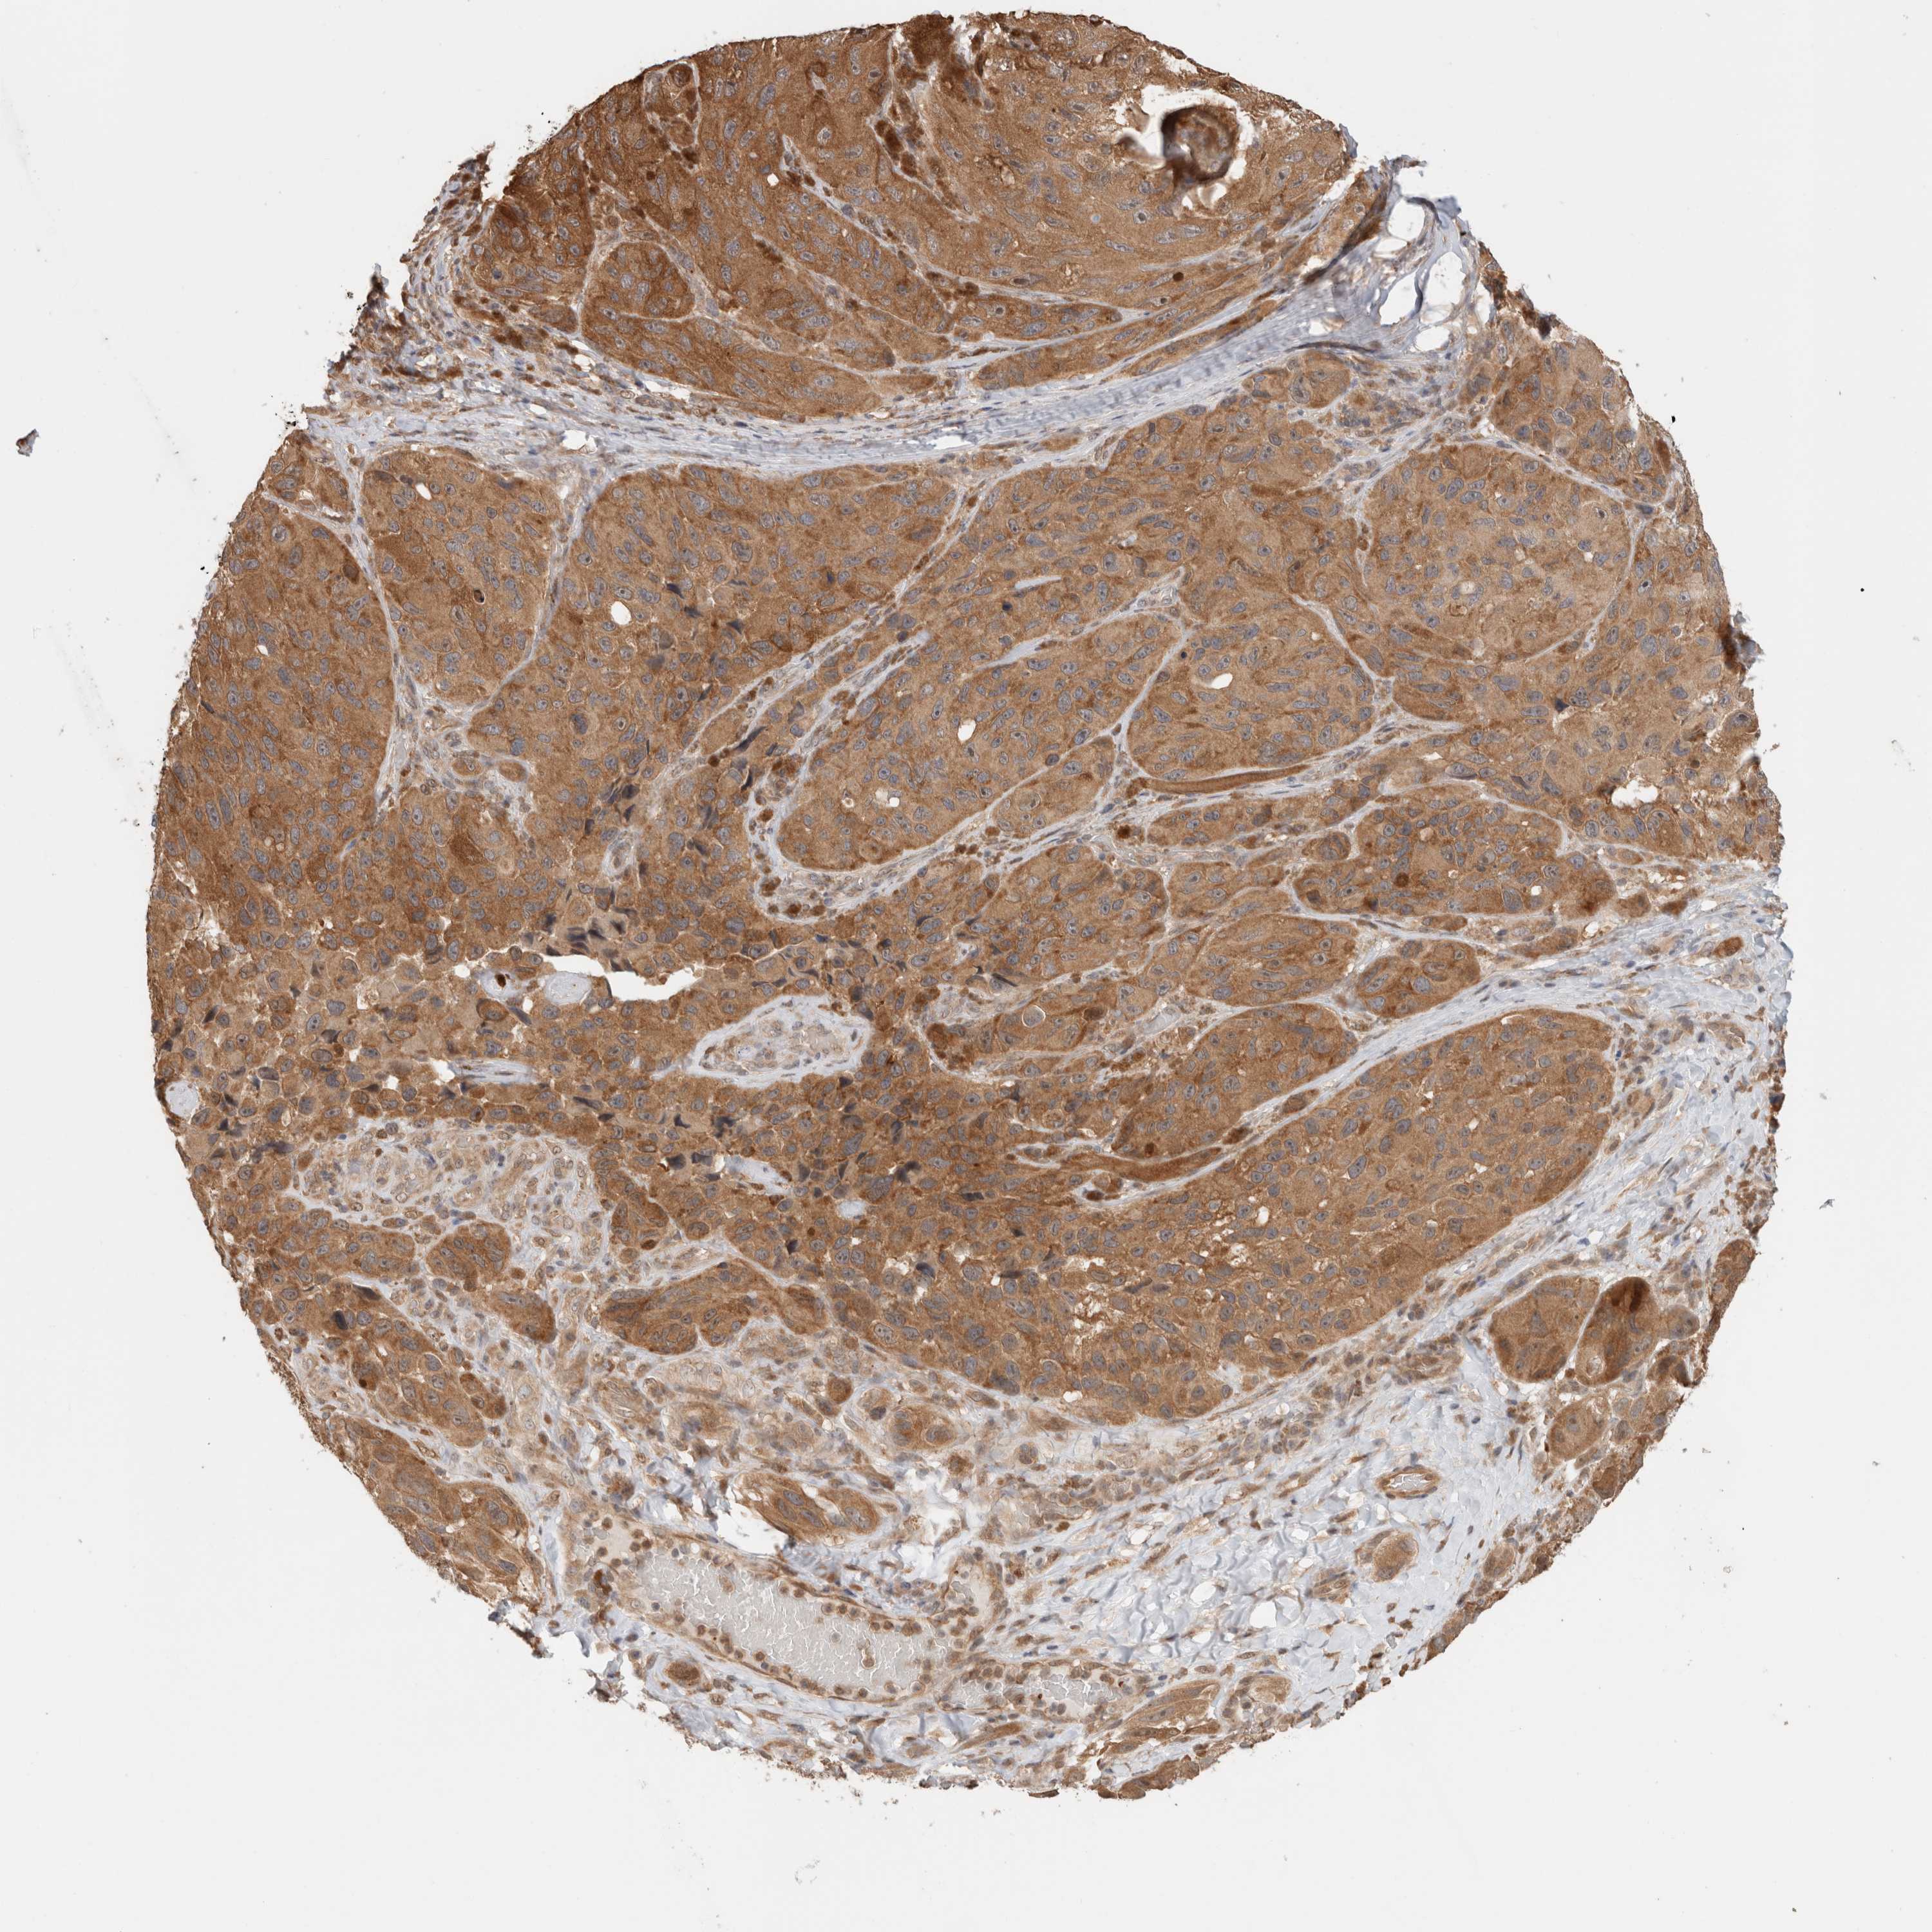

MELANOMA - Protein expressioni

A mouse-over function shows sample information and annotation data. Click on an image to view it in a full screen mode. Samples can be filtered based on level of antibody staining by selecting one or several of the following categories: high, medium, low and not detected. The assay and annotation is described here.

Note that samples used for immunohistochemistry by the Human Protein Atlas do not correspond to samples in the TCGA dataset.

Antibody stainingi

Antibody staining in the annotated cell types in the current human tissue is reported as not detected, low, medium, or high, based on conventional immunohistochemistry profiling in selected tissues. This score is based on the combination of the staining intensity and fraction of stained cells.

Each image is clickable and will lead to virtual microscopy that enables deeper exploration of all samples and also displays staining intensity scores, fraction scores and subcellular localization as well as patient and tissue information for each sample.

Staining

High

Medium

Low

Not detected

Intensity

Strong

Moderate

Weak

Negative

Quantity

>75%

75%-25%

<25%

None

Location

Nuclear

Cytoplasmic/membranous

Cytoplasmic/membranous,nuclear

Malignant melanoma, NOS

Malignant melanoma, Metastatic site